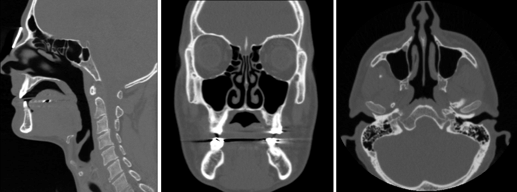

What are the 3 common views of a CT scan?

A

(1) Sagittal

(2) Coronal

(3 ) Axial